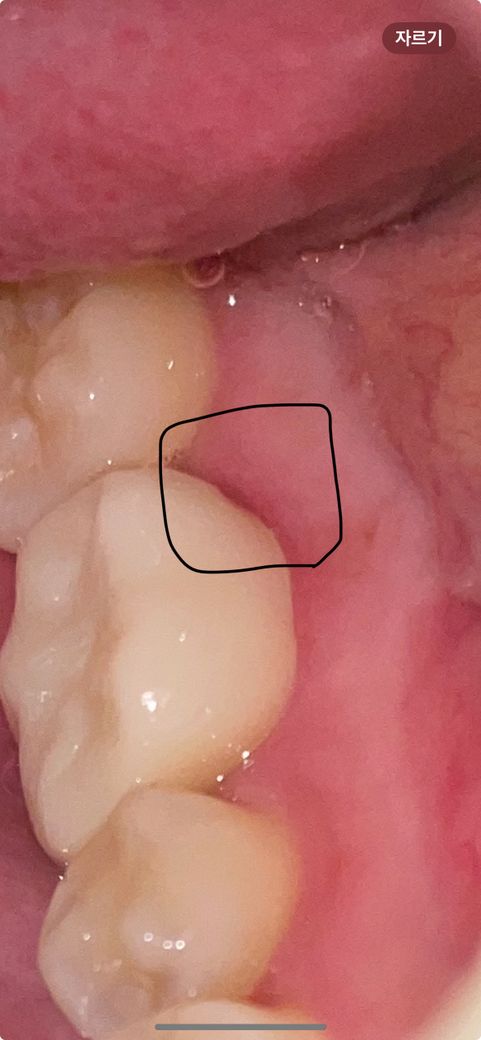

크라운 후 틈같은게 있어요 뭔가요??

어제 크라운 완전접착했어요

혀로 만져보다 이상한게 느껴져서 보니

저렇게 틈같은게 있는데 괜찮은건가요??

어제 치실을 하다가 접착제가 같이 나오긴했었는데

그거랑 연관이 있을까요? 저 틈사이로 세균이 들어갈 수도 있는걸까요 ㅠㅠ 아님 혹시 깨진걸까요?

• 1번 째 사진